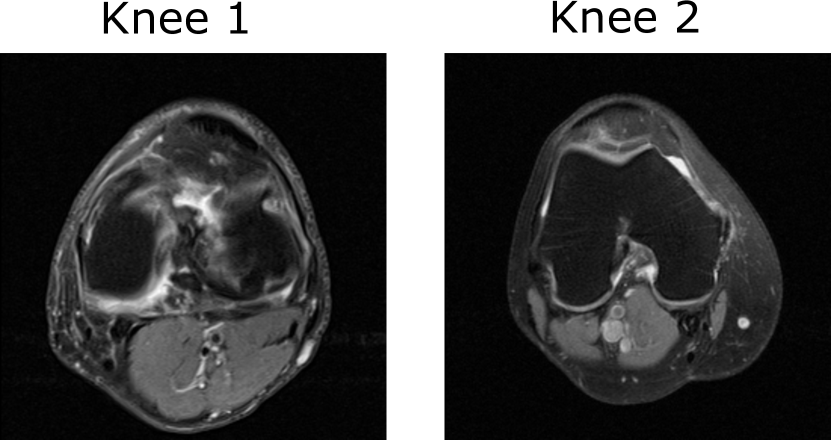

V-A Stylized imager that acquires incomplete Fourier space measurements

Refer to caption

Figure 2: The objects Knee 1 and Knee 2 with size 256×256256256256\times 256 from which noisy and incomplete k-space measurements were generated. Both the objects are displayed in the grayscale range of [0,1]01[0,1].